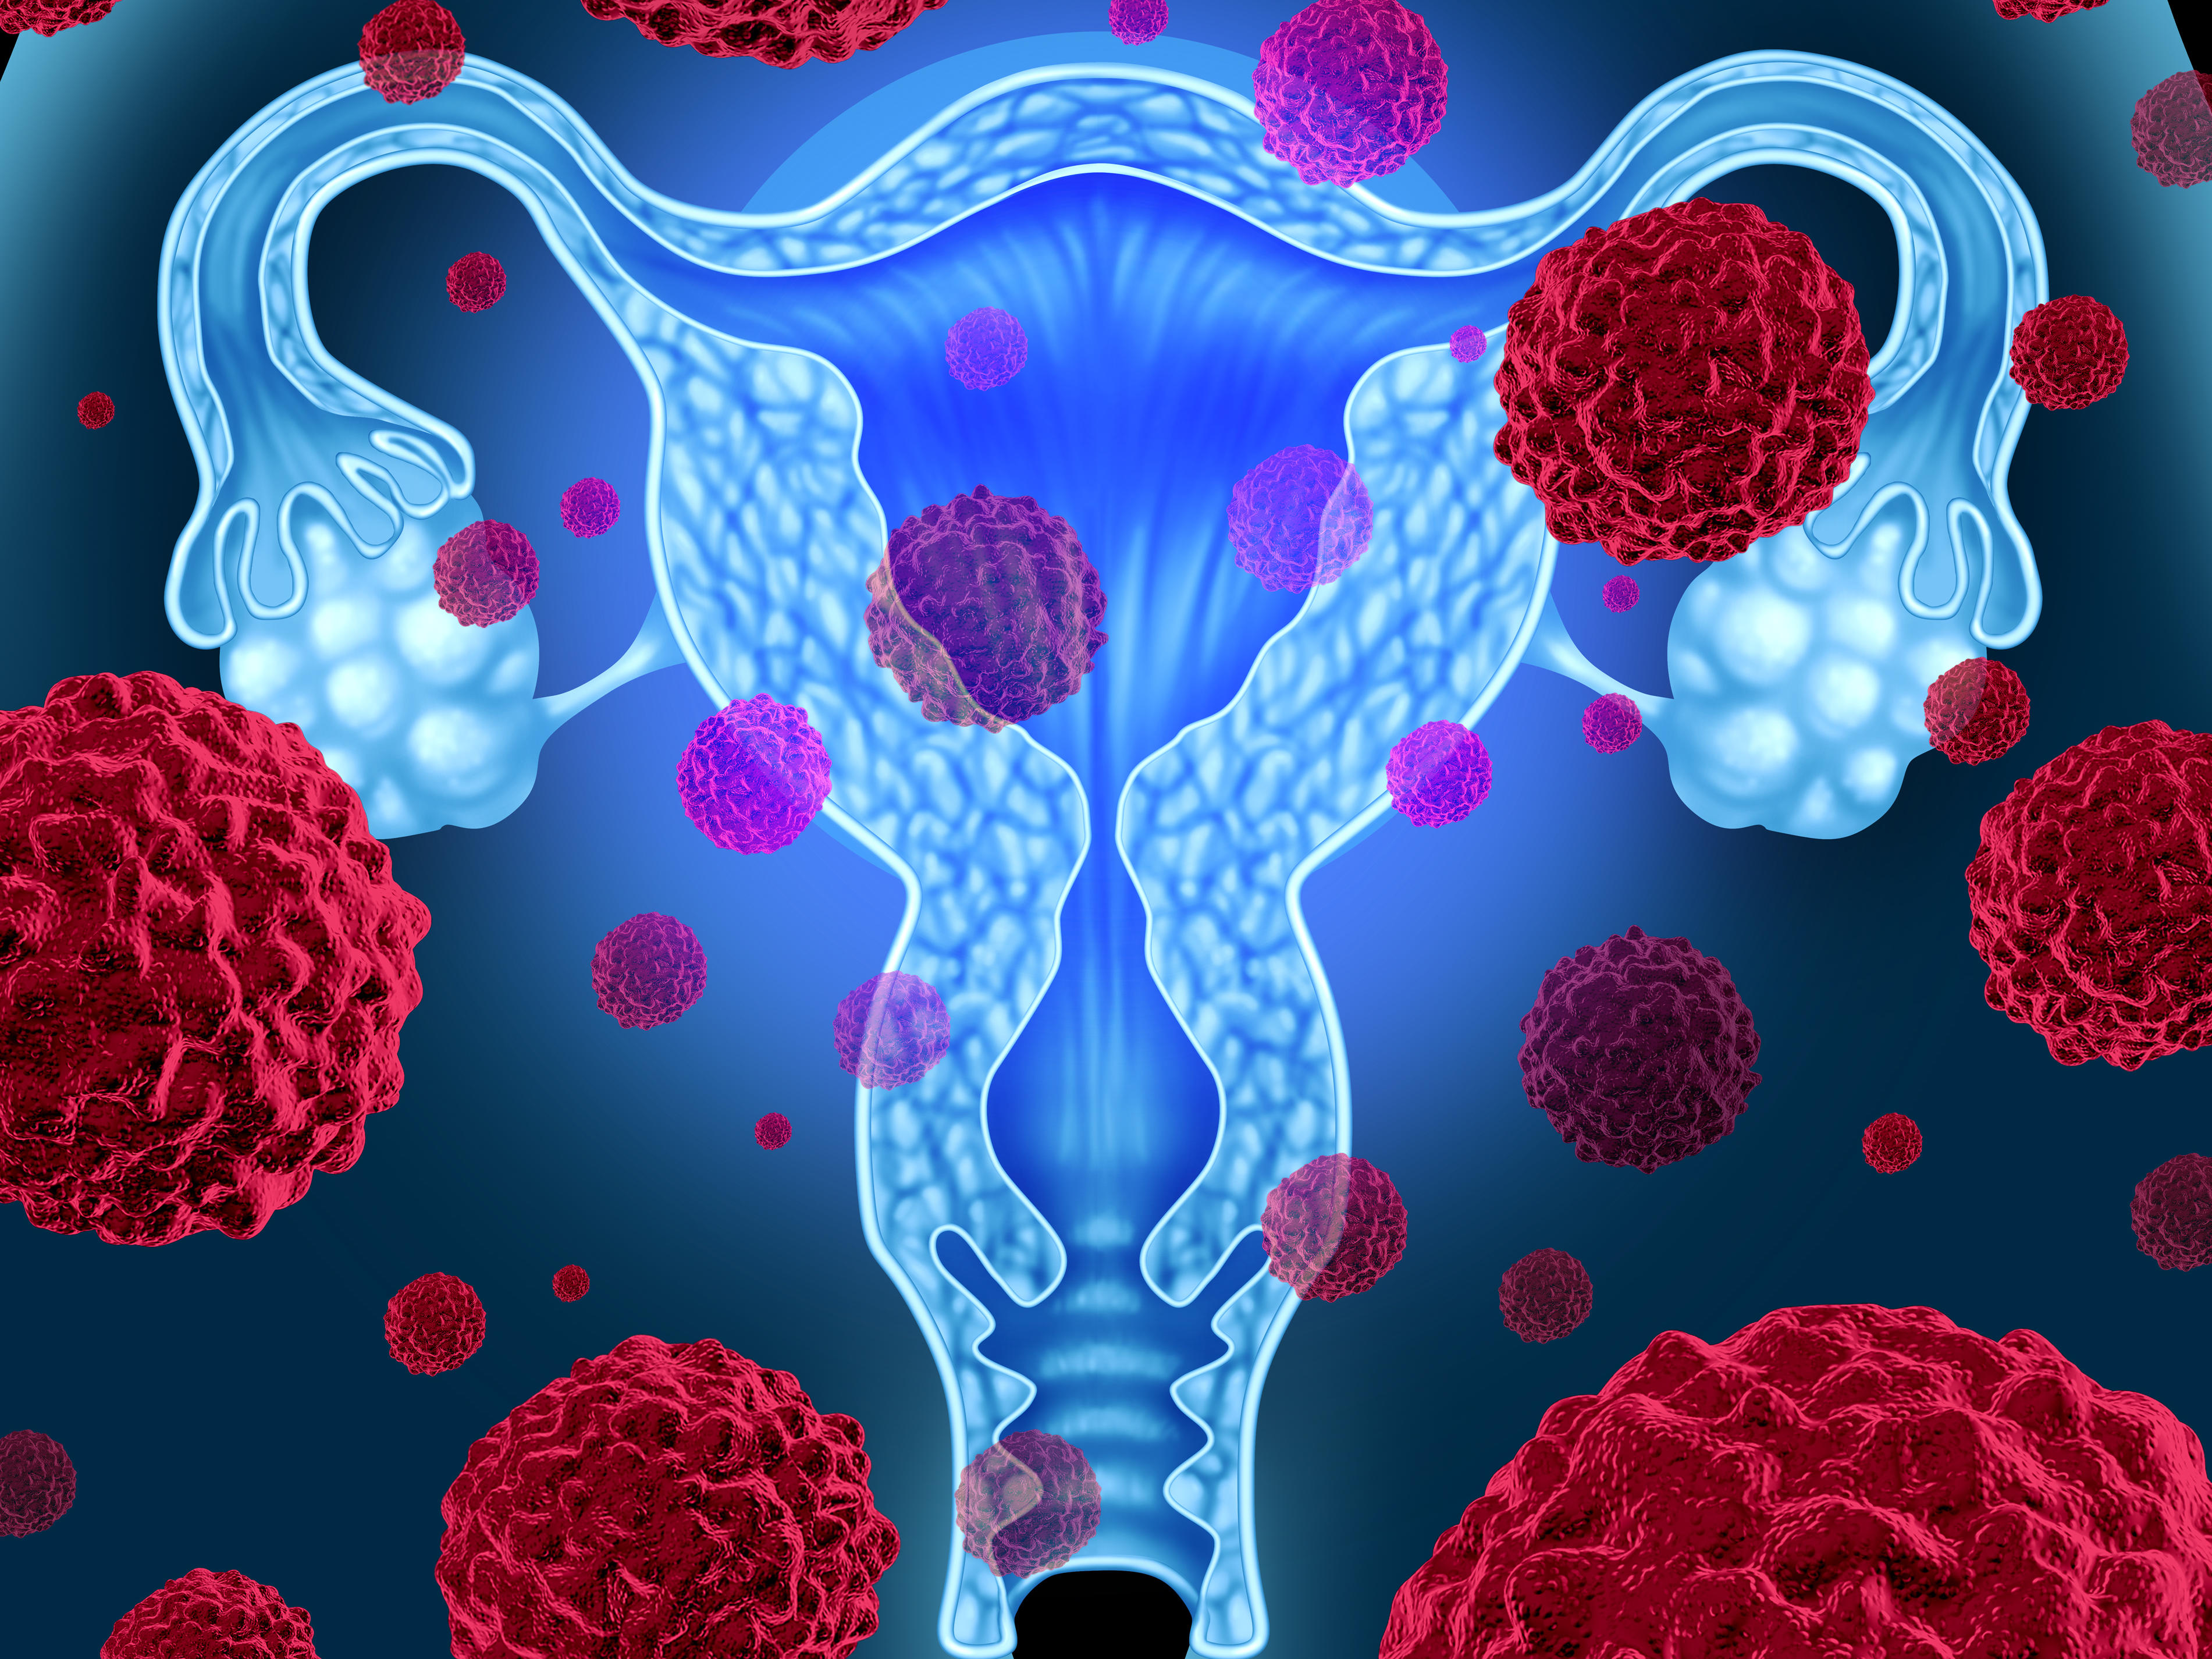

Факторы Риска ВПЧ: Визуальный Обзор и Информация